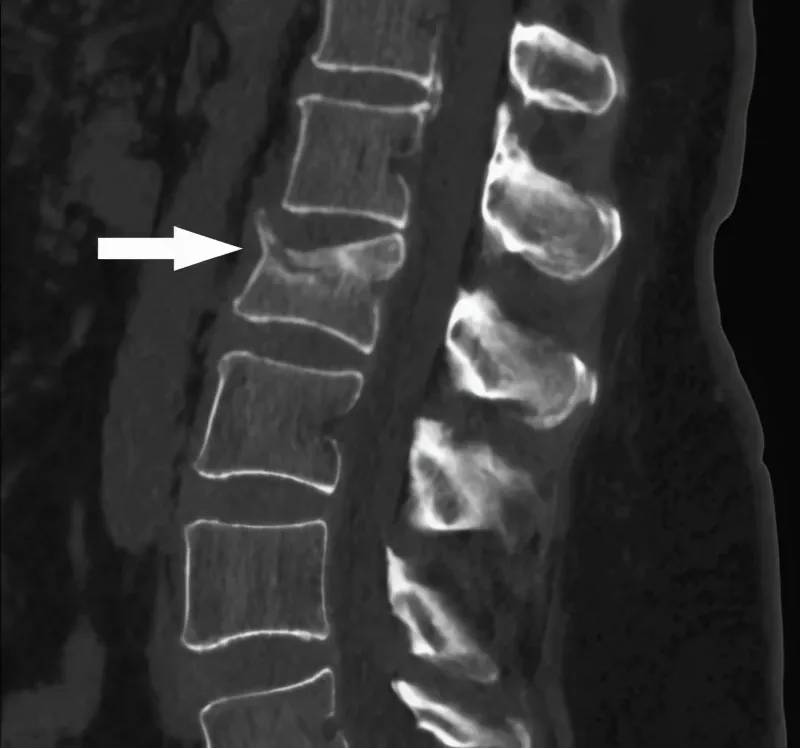

Роль КТ в диагностике остеопороза и отличие от других методов

Преимущества КТ

Компьютерная томография (КТ) позволяет получить детализированные трехмерные изображения костной ткани. Этот метод существенно превосходит рентгенографию в плане точности и информации о состоянии костей. КТ позвоночника позволяет выявить даже минимальные изменения в структуре костей, что критически важно для ранней диагностики остеопороза.

Возможность визуализации

Одним из ключевых достоинств метода является возможность визуализации не только самой плотности костей, но и их структуры. Это позволяет обнаружить наличие микропереломов и другие патологии, которые могут не быть видимыми при использовании других методов, таких как костная денситометрия.